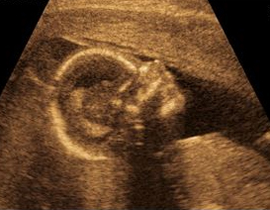

توصل فريق من أطباء أمراض النساء الهولنديين فى تقرير نشر اول امس الثلاثاء ، إلى أن ذاكرة المدى القصير تبدأ العمل لدى الجنين وهو بعمر 30 أسبوعا.

واستخدم يان نييويس، أستاذ أمراض النساء وفريقه في المستشفى التعليمي بمركز ماستريخت  الطبي ، تحفيزا صوتيا وحسيا لأرجل أطفال لم يولدوا بعد، لاكتشاف بدء عمل الذاكرة البشرية.

واكتشف الباحثون انه بعد سماع الطفل لصوت خاص أو شعر بلمسة خاصة لعدة مرات ، فإنه يتعرف عليها متى حدثت في المرة القادمة. وقال نييويس"لقد اتخذنا خطوة أخرى إلى الأمام في اتجاه فهم  كيفية تطور الأطفال في مرحلة ما قبل الولادة ".